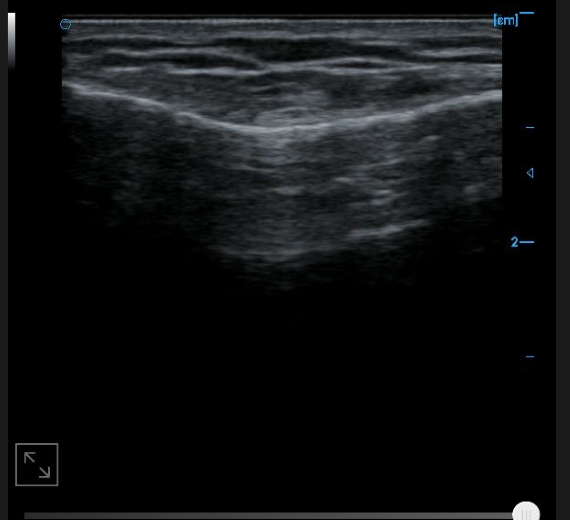

Knee collateral ligament B image